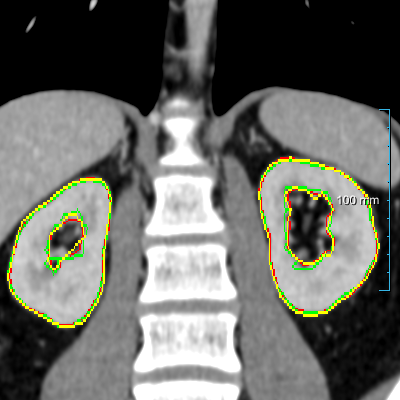

Refer to caption

(a) Patients without kidney abnormalities.

(b) Patients with kidney abnormalities.

Figure 3: Four examples of CT scans from the training set (dataset A) showing coronal sections with annotations in format 2 (see Figure 2(c)) where yellow and red overlays represent annotations of the parenchyma and kidney abnormalities, respectively. Note that all the patients have anomalies in the body (green arrows in the body), and both cases of (b) have only one kidney and contain kidney abnormalities. All the slices have a window center of 60 HU and a window width of 360 HU.

Samples of CT scans from patients included in this study can be seen in Figure 3. While Figure 3(a) depicts patients without kidney abnormalities, it highlights the presence of abnormalities in other parts of the body, such as liver tumors. Figure 3(b) shows patients with kidney abnormalities, as well as other abnormalities in the body, such as nephrectomy and collapsed lung.